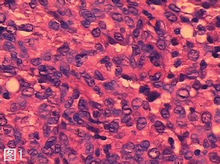

2.4 HPV 與宮頸癌 (cervical carcinoma)。HPV6、11、15、16、18、31、33、35、42、45、56、58和68型能感染女性生殖道,引發性傳播,如尖銳濕疣,能引發皮膚和黏膜鱗狀上皮增生及宮頸組織壞死。HPV16、18、31和45型與宮頸癌的關係甚為密切,85%宮頸癌及其癌前病變中發現HPV16和18型的DNA序列,其中70%為鱗狀細胞癌,15%為腺癌。HPV16或18型的DNA可整合到宿主細胞的DNA中。用分子雜交技術從宮頸癌組織刮取的細胞和宮頸癌的細胞株均能檢出HPV。HPV18型DNA在宮頸癌細胞株(SW756、C4-1、Hela細胞)中表達也獲得了實驗室證實。在人體細胞記憶體在一類與癌基因對立的抑癌基因,如RB基因(視網膜母細胞瘤基因)和p53基因 (p53基因位於人17p13-1q染色體上),相應編碼Rb蛋白和p53蛋白,均具有抑制細胞生長和促進細胞分化作用。HPV16和18型病毒E1、E6、E7基因編碼的E1、E6、E7蛋白能與Rb蛋白、p53蛋白結合,使Rb蛋白和p53蛋白變性,失去對腫瘤抑制作用,從而促使細胞轉化,導致細胞增殖和癌變。

宮頸癌是最常見的婦科腫瘤之一,發病率僅在乳腺癌之下。宮頸癌的發生與性行為有關,多見於多性伴人群,腫瘤細胞侵襲子宮頸基質、子宮、陰道和子宮旁組織,沿淋巴轉移至盆腔,沿血行轉移至肺、肝、骨和腦。用桿狀病毒表達系統獲得的VLP(virus like particles)製成HPV疫苗前景良好。疫苗能有效預防HPV感染,對早期感染者也有治療作用。HPV16型L1蛋白50μg肌注志願者能誘導機體產生高滴度中和抗體。